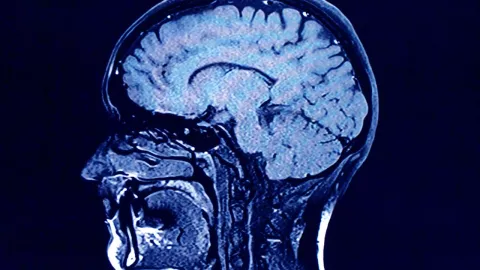

¡Increíble caso! Médicos de Australia realizaron un procedimiento quirúrgico que quedará enmarcado en la historia de la medicina, pues por primera vez, se logró sacar un gusano vivo del cerebro de una persona, la cual comenzó a presentar diversas afectaciones médicas por este hecho.

Fue la doctora neurocirujana Hari Priya Bandi, quien logró el increíble descubrimiento en el cual sacó el gusano de hasta ocho centímetros de una mujer de 64 años de edad, la cual había acudido al hospital para un procedimiento quirúrgico.

Luego de este descubrimiento, el cual se presume ser el primero en todo el mundo, expertos del Hospital de Canberra ya comenzaron con los estudios y análisis para saber la procedencia del parásito que se encontraba completamente vivo en el cerebro de la mujer de 64 años de edad.